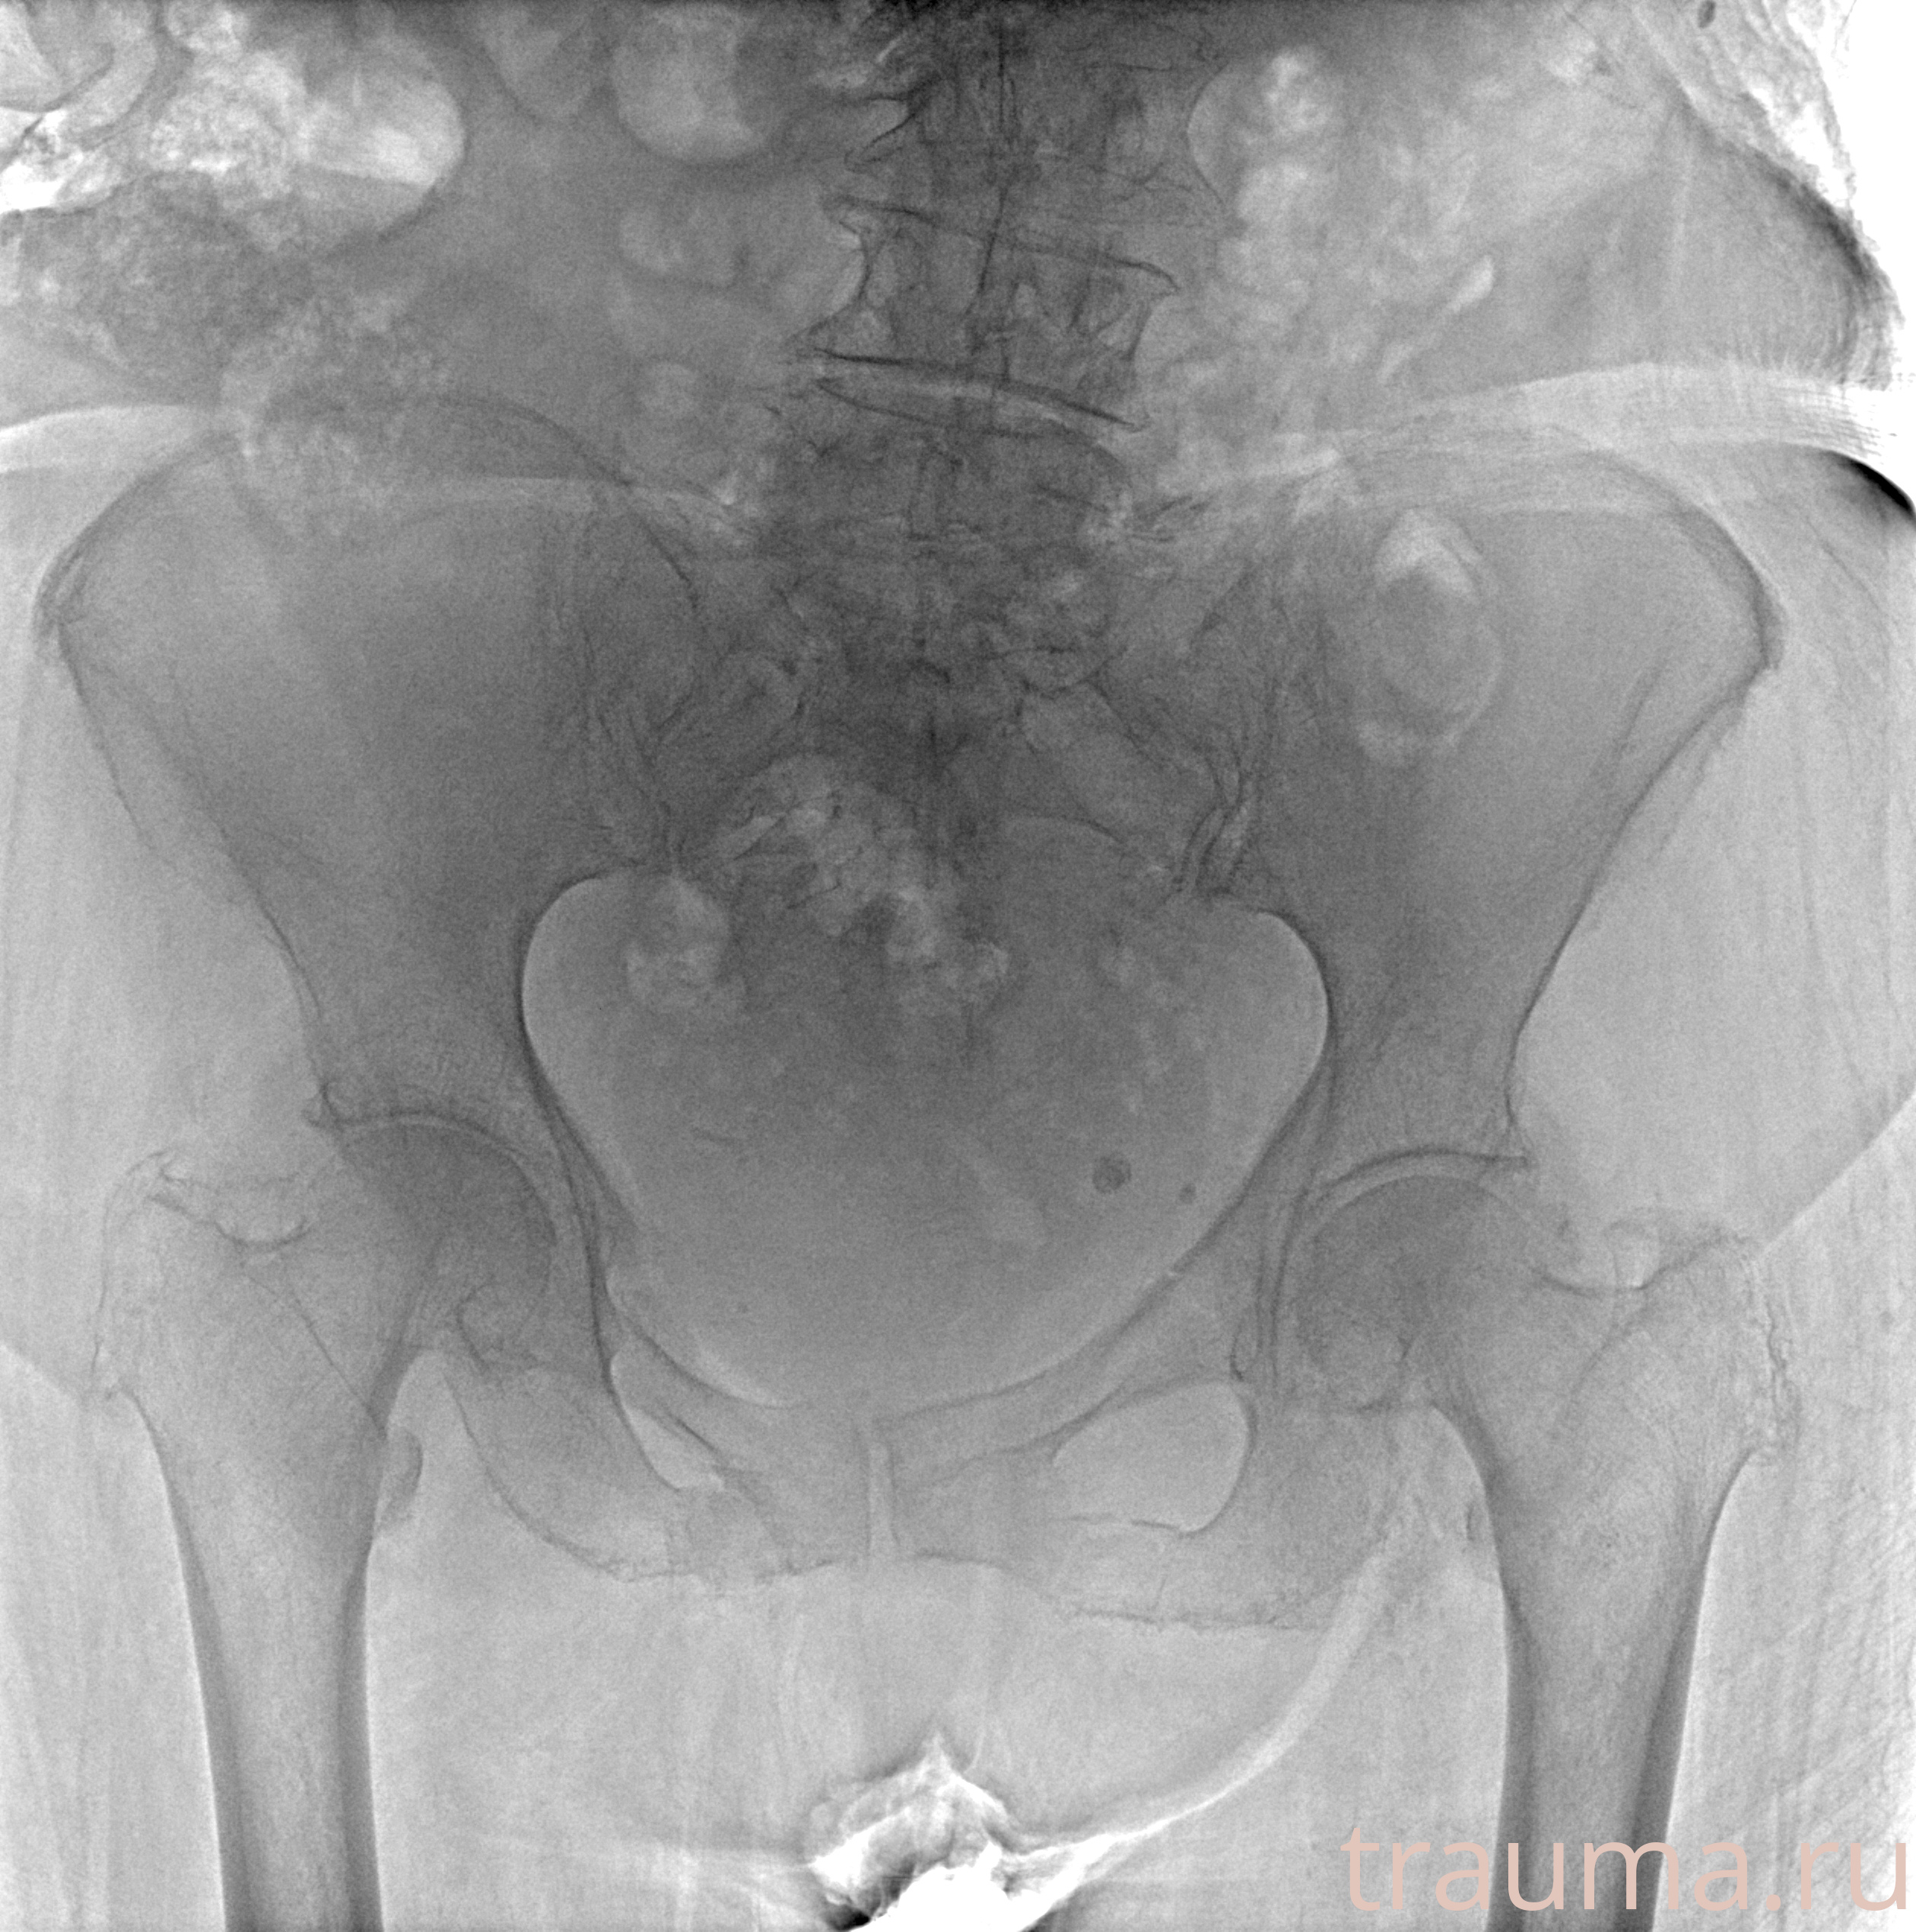

Рентгенограммы

Рентген на дому: по вашему адресу приезжает врач-рентгенолог, травматолог-ортопед с мобильным рентгеновским аппаратом, проводит диагностику травмы или заболевания, делает необходимые рентгенограммы, дает рекомендации по дальнейшему лечению. Получить качественные снимки в домашних условиях возможно благодаря уникальной методике, разработанной МосРентген Центром для института  Склифосовского